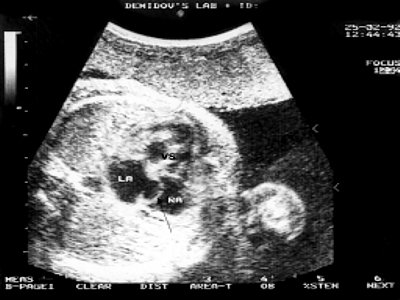

Рис. 1. Четырехкамерное сечение сердца плода в 30 недель гестации. Опухоль сердца прорастает миокард задней стенки левого желудочка, межжелудочковую перегородку. Межпредсердная перегородка уплотнена, овальное окно не функционирует (стрелка).

LA - левое предсердие, RA - правое предсердие, VS - межжелудочковая перегородка.